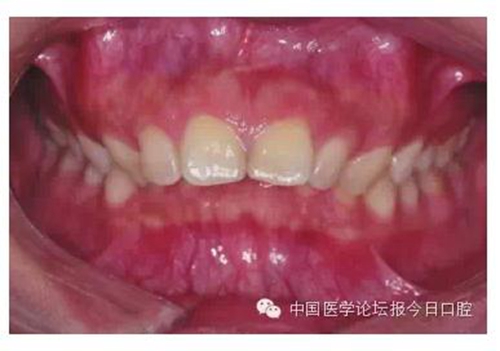

圖1 牙冠明顯舌傾,容易形成骨皮質(zhì)支抗者,可考慮選擇正轉(zhuǎn)矩度的尖牙托槽

由于有很多患者在微笑時“頰廊”會比較明顯(圖2),這種情況往往預(yù)示著其上牙弓狹窄或上頜后牙過于舌傾(圖3),從而影響了微笑的美觀,正畸時有必要直立上頜后牙,這樣就可以創(chuàng)造飽滿的微笑,這類病例可以考慮選擇上頜前磨牙的零度轉(zhuǎn)矩,有效實現(xiàn)上頜后牙的直立。

圖2 患者在微笑時“頰廊”

圖3 存在“頰廊”者的口內(nèi)情況